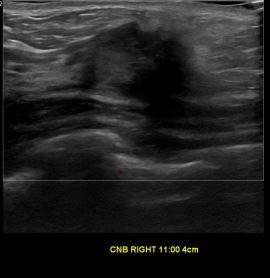

상기환자는 우측 유방 만져지는 멍우리 있어 정밀검사 위해 내원하신 40대 초반

여성분으로 의심스러운 우측 유방혹 조직검사 시행해 유방암으로 진단 되었습니다